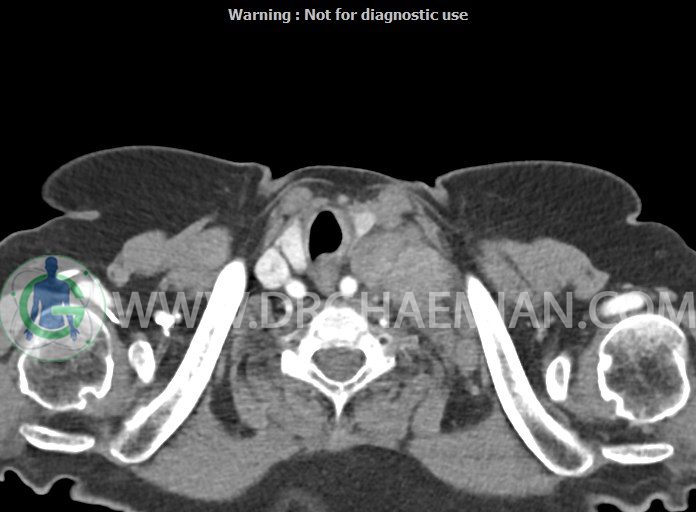

در سی تی اسکن اسپیرال از گردن با تزریق (مولتی دیدکتور 16 با مقاطع ظریف و بازسازی های ساژیتال و کرونال):

– تصویر توه های نسج نرمی oval shape متعدد با Enhancement تقریباً هوموژن، قرار گرفته در سمت چپ گردن، در لول غضروف کریکوئید با اثر فشاری شدید و compression ورید ژوگولار، با گسترش تحتانی به اینفراکلاویکولار چپ، به حداکثر ابعاد 28x50mm (با Enhancement مختصر هتروژن در این توده)

در درجه اول مطرح کننده لنفادنوپاتی متاستاتیک مطرح می باشد بالین، تومورهای منشأ گرفته از غلاف عصبی زنحیره سمپاتیک چپ گردنی، شبکه براکیال و لنفوم نیز در DDX قرار دارند. لذا نمونه برداری بافتی جهت بررسی بیشتر توصیه می شود.

– اسکولیوز مهره های سرویکال با تحدب به راست، احتمالاً در زمینه اثر فشاری توده های مذکور

مشهود است.